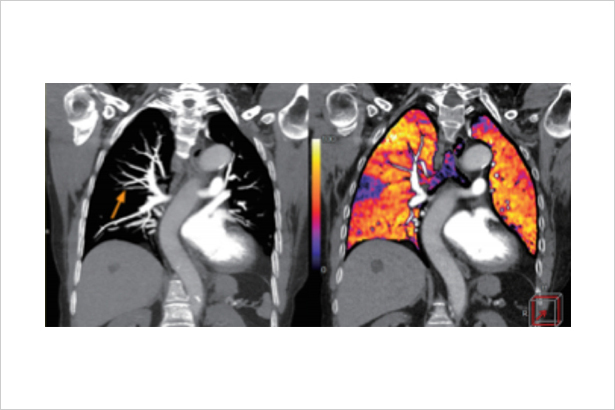

秉承佳能医疗超高端640层CT的AI同步轨道扫描技术与柔性扫描与彩色成像技术,在不增加扫描代价和患者辐射剂量代价的前提下,利用平扫和增强数据进行柔性的器官配准,0键式地得到彩色碘图等有价值的诊断信息,更敏感地发现病灶和淹没在器官背景的微小血供变化。

在柔性彩色肺部成像下,微小的亚段肺动脉栓塞引起的肺部血流灌注异常被敏感地发现。